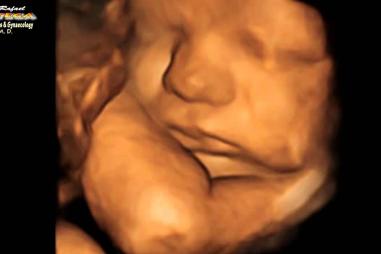

Kalifornia chce dať homosexuálom "právo" na umelé oplodnenie bez ohľadu na potreby detí

25.06.2023 USA

(LifeSiteNews) — Niektorí LGBT aktivisti už nejaký čas trvajú na tom, že homosexuálne páry majú právo mať deti, napriek tomu, že si to vyžaduje účasť tretej strany. Z tejto novej požiadavky…